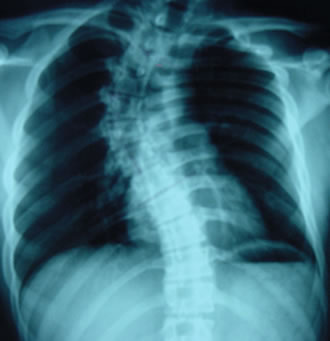

瀚群 骨科医疗中心陈怡孜医师表示,现代人常有腰酸背痛的毛病,很多都与脊椎有关。脊椎侧弯的病患,从X光片观察会发现脊椎是呈现C型或S型弯曲。临床上最常见 到不明原因的特发性脊椎侧弯,这种病患通常是天生性体质,且因后天姿势不良而加重症状,最常发现于10至18岁的青少年。

脊椎 侧弯的治疗,会根据侧弯严重程度而有所不同。陈怡孜医师表示,一般会经由X光片来测量,判断侧弯的位置是在胸椎或腰椎,或是两者皆有。此外,量出的角度若 小于10度属于正常范围,10至20度的轻度病患,必须密切追踪,平时可多游泳、吊单杠来强化肌力,让身体两侧的肌肉平衡,也可利用腰椎牵引器协助矫正。